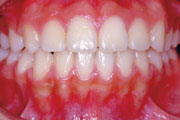

一般矯正の症例

症例2:乱杭歯(叢生)